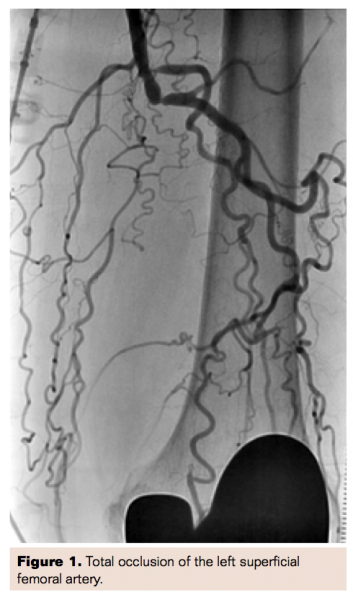

With the guidance of the OCT, the Ocelot catheter was successful in penetrating through the cap and the first centimeter of the total occlusion while remaining intraluminal (Figure 2). We were unable to make further progress despite increasing the speed of the Ocelot device and using a more supportive wire (Astato 20 g).

Starting the intervention intraluminal makes the use of the Wildcat the more aggressive device, safer and more likely to remain intraluminal. We have found from series of these cases that the Ocelot is very helpful in penetrating the proximal cap and first 1 cm to 2 cm of the CTO and when it could not be advanced any further, exchanging it for the Wildcat to overcome the rest of the occlusion. We believe that starting intraluminal with the Ocelot facilitates the Wildcat to successfully open the CTO while remaining intraluminal and avoiding dissections and perforations.